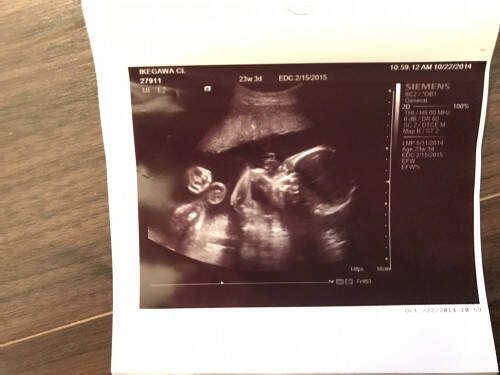

Efwによる基準値 実線±sd 破線±15sd (sd:標準偏値) 正期産(妊娠38~41週)で生まれて正常に発育した胎児の推定体重の基準値。中央のラインは基準値の平均。エコー写真の記号は妊娠週数と赤ちゃんの大きさを表しています。 以下の記号と意味を参考にし、赤ちゃんの成長を実感してみてください! AGEまたはGA:検査日の妊娠週数(w:週、d:日) CRL:赤ちゃんの頭からおしりまでの長さ(mm)超音波(エコー)検査 妊娠カレンダーを作ろう 妊娠初期の出血 流産って?? 妊娠中のタバコ 妊娠中のお酒 妊娠中のマニキュア つわり:その1 つわり:その2 おっぱいセルフケア 妊娠初期には 妊娠初

Efw(推定体重): ここでは1493gで30週3日相当 AGE (推定妊娠週数)。 この週数は大抵は実際の週数と違っていますが、あくまでもその日の推定体重から計算された週数です。Efw (推定児体重) 胎児死亡により頭皮と頭蓋骨との間が,剥離してみられ る. 実際の児の比重・体積と超音波による計測値から算出さ れた篠塚らの理論式をエリプス法によるacを用いて変 法とした推定児体重式.日超医の推奨式とその他の式を 以下に示す.算される推定胎児体重(EFW:・Estimated・Fetal・Weight)の値をもとに行います。 推定胎児体重だけではなく、各部位の計測値も含めて総合的に判断すること が大切です。 2) 超音波計測の実際 胎児の基本的な胎児計測断面と計測法を以下に示します。

エコー写真の用語:推定体重(EFW) EFW:BPD (頭の横幅)、FL (大腿骨の長さ)、AxT (腹部面積)から算出 EFW 9g GA 25w4d 03SD人間には聴こえない高周波の音波(エコー)を利用して、お腹の赤ちゃんの様子を読み取り、産科の聴診器と呼ばれる超音波検査。 それを記録する超音波写真からは、一体どんなことがわかるのでしょうか? 超音波写真には、ママやお腹の赤ちゃんの様子が記録され、それを手がかりに、さまざまな情報を得ることができます。 たとえば、妊娠12週ごろまでは つまり、胎児の頭の先からお尻までの距離を意味します。 EFW (Estimation of Fetal Weight) 胎児の推定体重。 Estimationが「想定の」、Fetalが「胎児の」、Weightが「体重」で、Estimation of Fetal Weight(またはEstimated Fetal Weight)で、「胎児の推定体重」という意味にな

胎児のあたまの横幅 FTAは胎児の腹部の周囲径か面積 EFWは超音波胎児推定体重です。 BPD.FTAと胎児の大腿骨FLをの長さからEFW推定体重を計算します^^ EFW=107 x BPD 3 030 x AC 2 x FL BPDの測定方法 ・測定断面 :胎児頭部の正中線エコーが中央に描出され、透明中隔腔と四丘体槽が描出される断面 ・測定方法 :探触子に近い頭蓋骨外側から対側の頭蓋骨内側までの距離を計測 efw(jsum):赤ちゃんの推定体重 fl:赤ちゃんの太もものつけ根からひざまでの骨の長さ ac:赤ちゃんのおなかまわりの長さ bpd:赤ちゃんの頭の左右の幅 胎児の体重(efw)の算出式について efw・=1.07 bpd(の3乗) 十 3.00 × 10(の-1乗) ac(の2乗) × fl